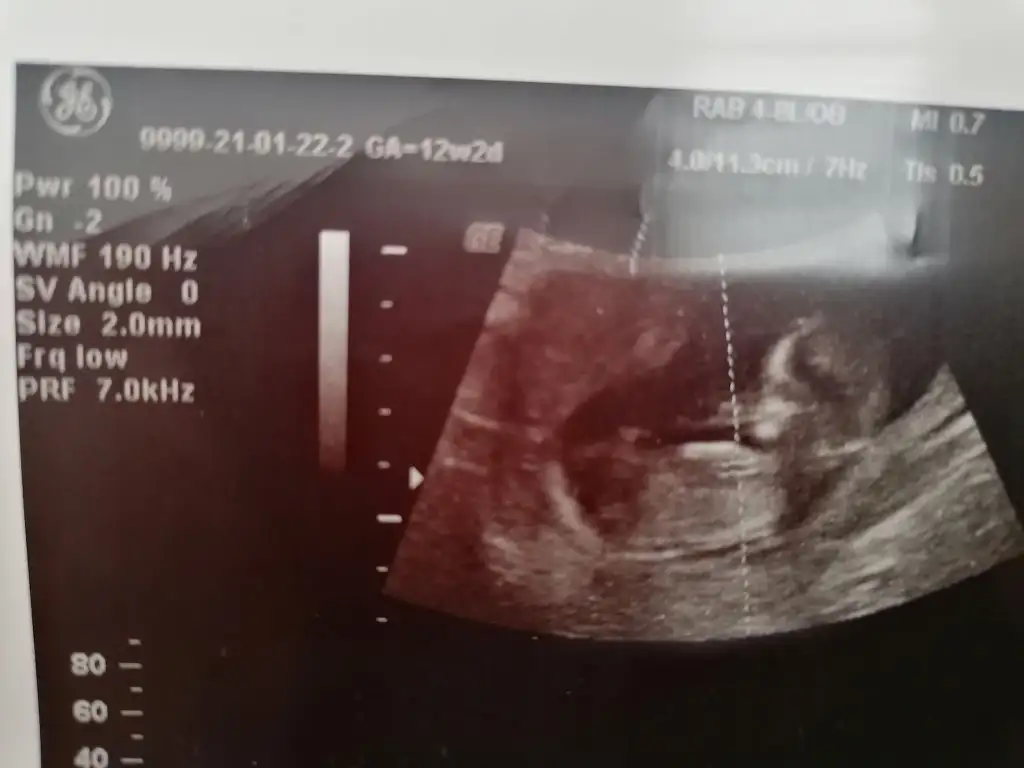

Merhaba Ikra meyra Ikra meyra bugun tekrar kontrol gittim atıyorum 12+2 🤗

Eklentiler

• IMG_20210122_124028.webp

IMG_20210122_124028.webp

17,6 KB · Görüntüleme: 83

• IMG_20210122_124005.webp

IMG_20210122_124005.webp

26,3 KB · Görüntüleme: 84